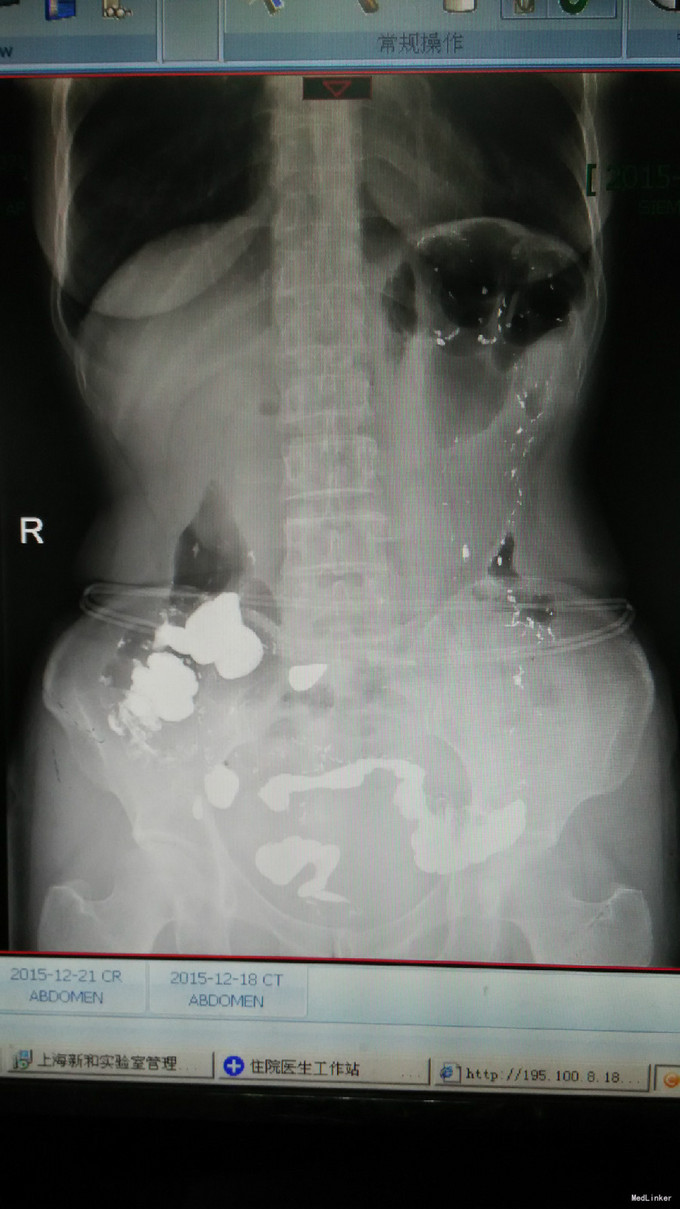

查体及专科情况无特殊 胃肠动力研究中心结肠传输时间检测:48小时和72小时钡条排除率为0%,考虑慢传输。 直肠肛管测压/感觉检测报告:1.肛门指检可见外痔,未及内痔,肛缩有力,力排松弛欠佳;2.测压:肛管静息压正常,直肠静息压偏高,缩肛时肛管压力升高,持续力可,模拟排便时直肠压力升高,肛管压力升高,呈矛盾性收缩;3.感觉:各项感觉阈值正常。 协和医院肠镜:结肠粘膜黑变病;混合痔。 钡剂灌肠:经肛管插入顺利,钡剂经直肠、乙状结肠、降、横、升结肠到达回盲部,乙状结肠较长约47.0cm(该患者应为33.0cm),并走行迂曲,全段钡剂通过顺利,未见明显龛影及充盈缺损影。排便后复查,阑尾显示清晰。乙状结肠冗长。 腹部增强CT: 1.肝右后上段包膜下0.6×1.2cm,CT值约-52HU,内可见小片状高密度影,增强未见明显强化,考虑错构瘤; 2.肝内见多发大小不等低密度影,未见强化,考虑囊肿,较大者6.6cm; 3.胆囊充盈,胰腺、脾脏及双肾未见明显异常; 4.肠管未见明显扩张及梗阻征象; 5.膀胱未见明显异常; 6.陶氏腔少许积液; 7.腹、盆腔未见肿大淋巴结。